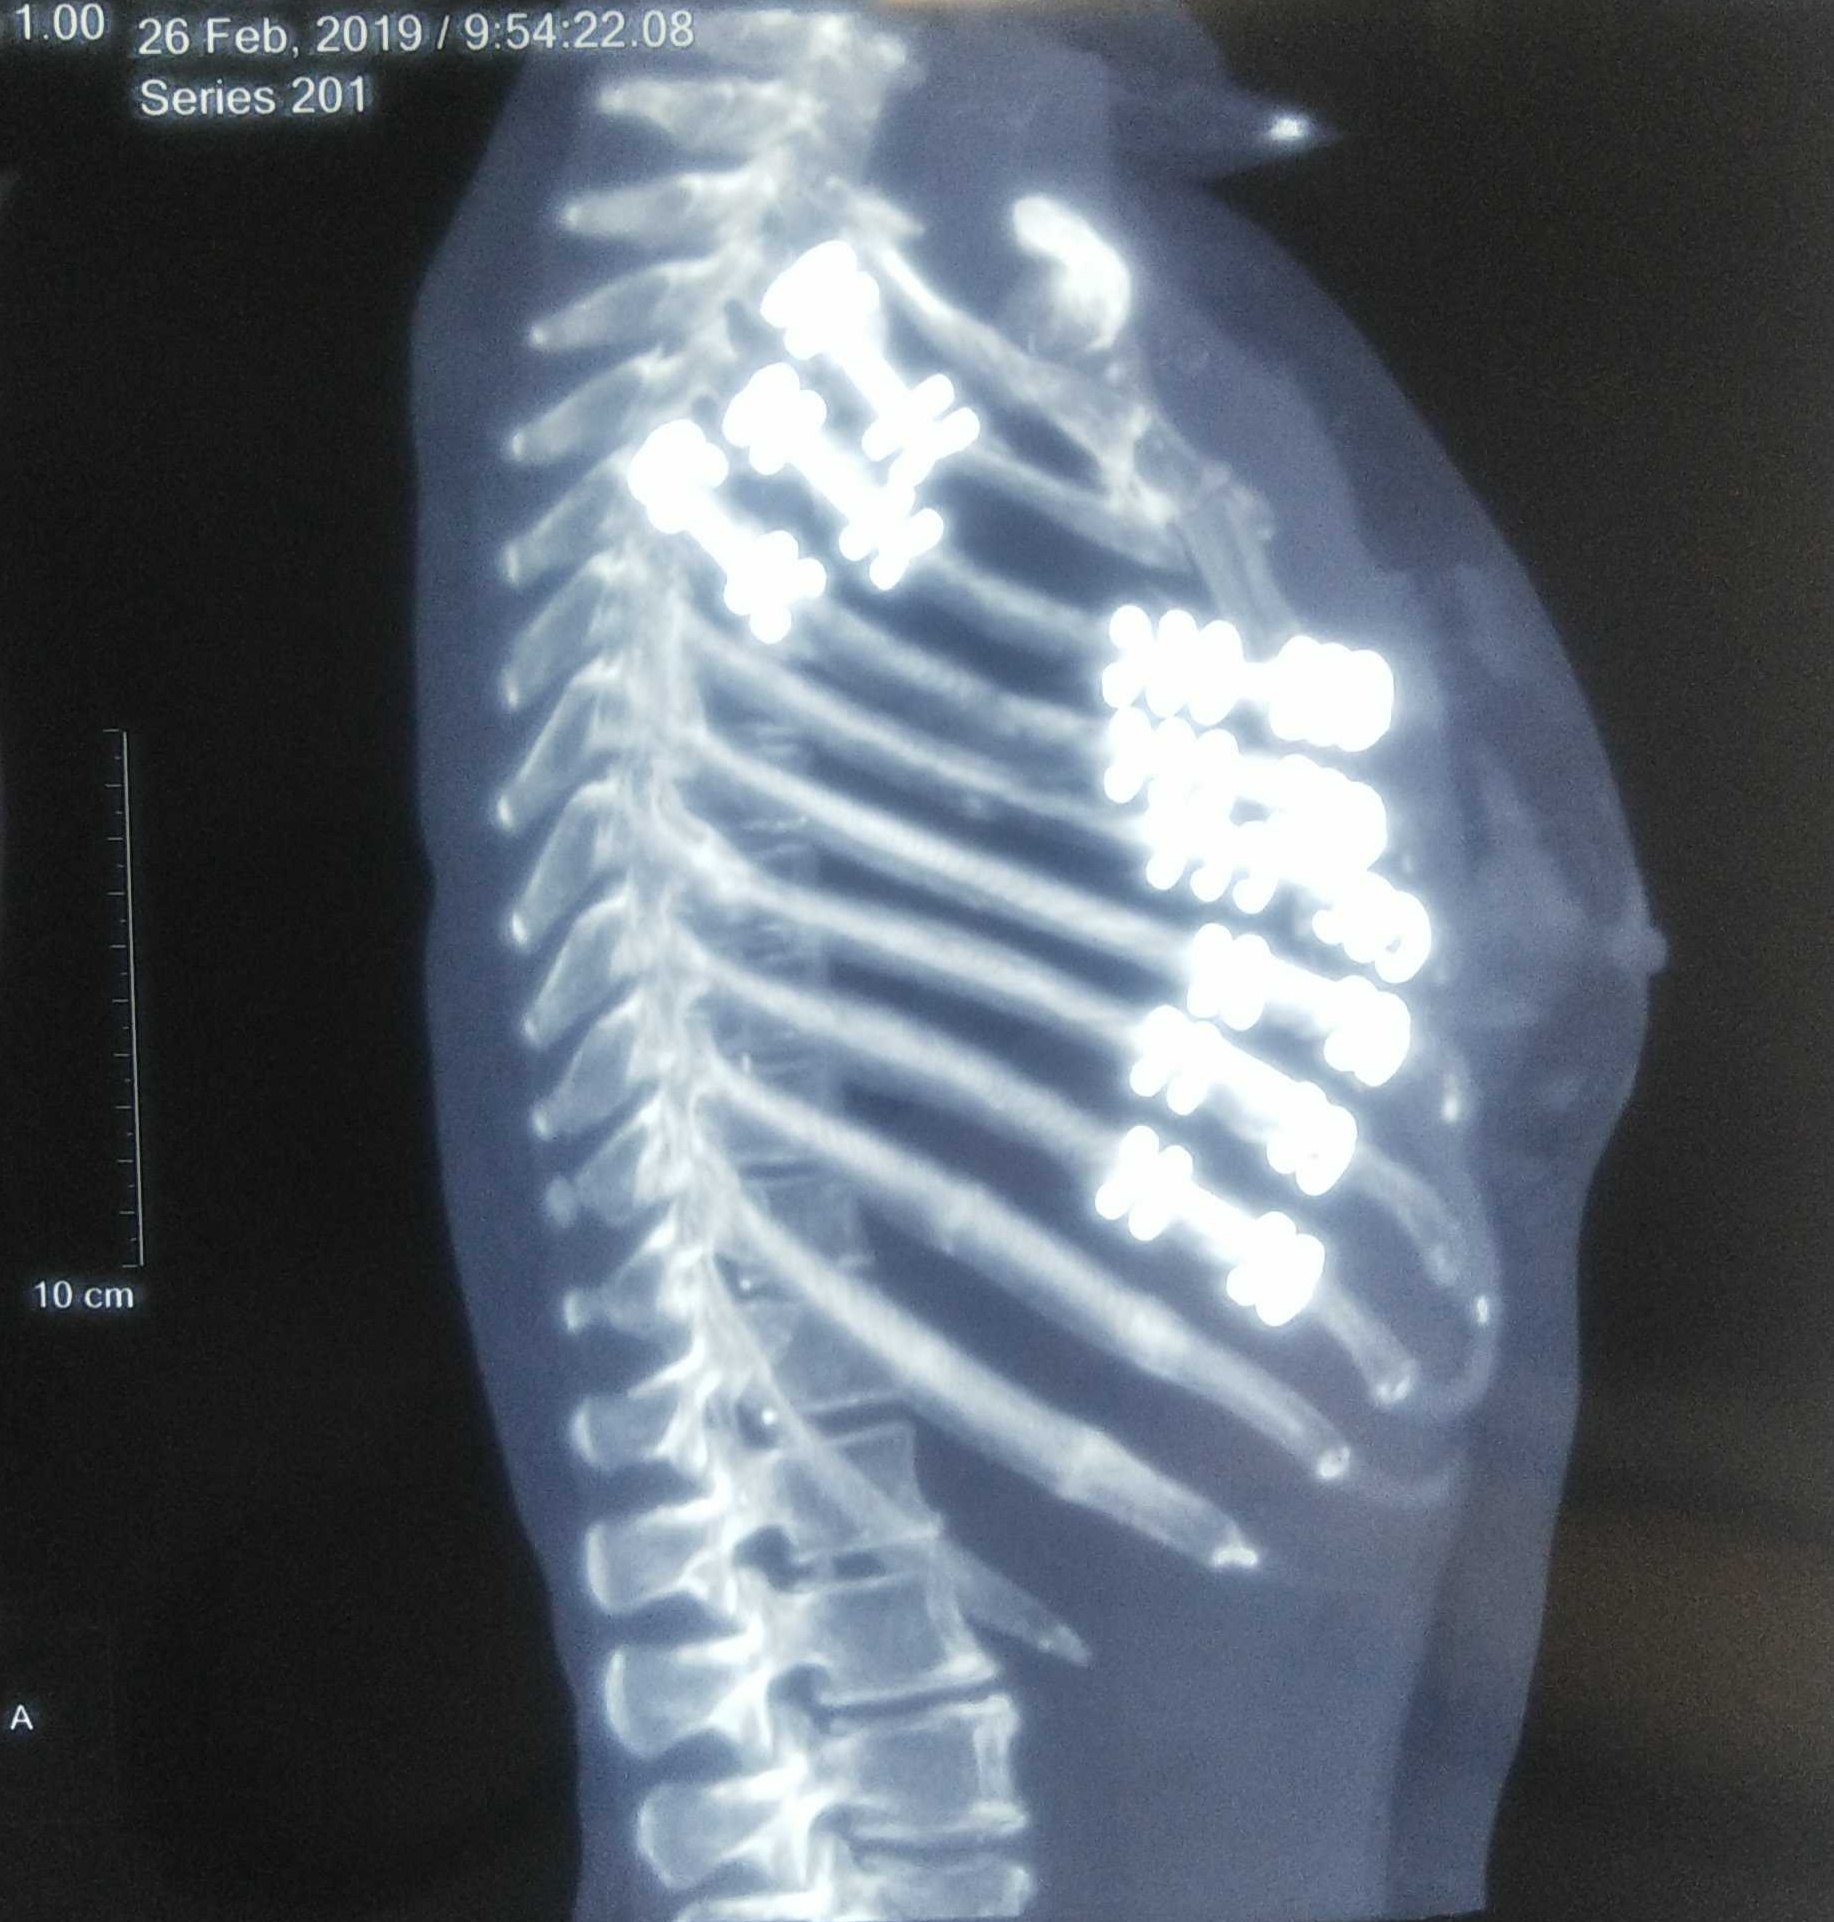

来院時 Ct a 左多第 3 11肋骨骨折を認め 第 9 11肋骨は 2 カ所で骨折していた 矢印 Download Scientific Diagram

左边第9块肋骨的胸部x光破裂权利后部第6块肋骨和可能的破裂侧向方面库存图片 图片包括有左边第9块肋骨的胸部x光破裂权利后部第6块肋骨和可能的破裂侧向方面

胸部x 線骨折右後第6肋骨和左9肋骨可能骨折側側照片檔及更多人照片 Istock